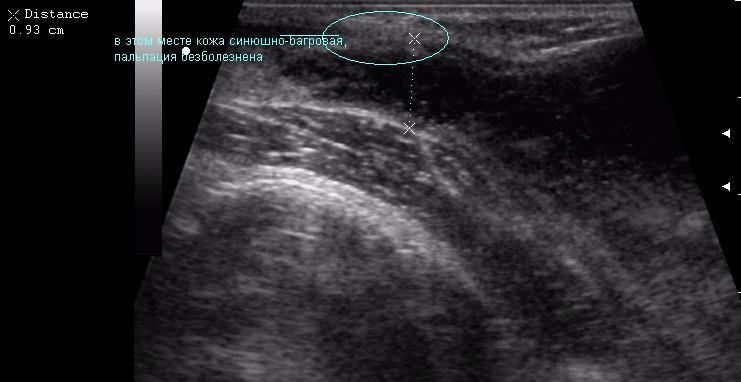

В клинику обратилась мать 11-летней девочки с жалобами на появление припухлости в подключичной области справа. Впервые заметили в феврале. За 4 месяца не интенсивный рост образования, с переходом на переднюю поверхность плеча, где кожа над ним на ограниченном участке (1.5-2см) имеет багрово-синюшную окраску.

достоверной связи с мышцами не увидела. Но на задней проекции включения определяется солидное образование. это может быть лимфоузел?